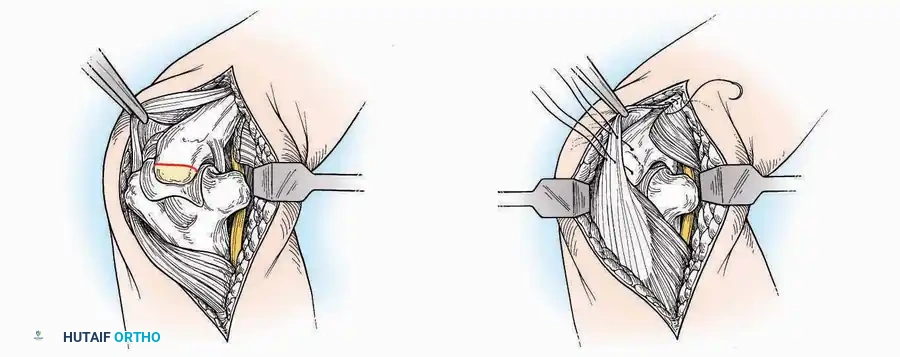

Anterolateral Approach

The anterolateral approach is widely considered the "universal incision" for the foot and ankle. It provides unparalleled access to the ankle joint, the talus, and the majority of the tarsal articulations, while safely avoiding the major anterior neurovascular bundle. The only tarsal joints inaccessible via this route are the naviculocuneiform joints (specifically the medial and intermediate).

Indications: Total talectomy, triple arthrodesis, ankle arthrodesis, and open reduction of complex talar neck fractures.

Surgical Technique:

* Incision: Begin over the anterolateral aspect of the leg, medial to the fibula and 5 cm proximal to the ankle joint line. Carry it distally over the joint, crossing the anterolateral aspect of the talar body and the calcaneocuboid joint, terminating at the base of the fourth metatarsal.

* Superficial Dissection: Incise the superficial fascia and the superior and inferior extensor retinacula down to the periosteum of the tibia and the ankle joint capsule.

* Vascular Ligation: This trajectory usually requires the identification and ligation of the anterolateral malleolar and lateral tarsal arteries.

* Nerve Protection: Retract the skin edges carefully. Identify and protect the intermediate dorsal cutaneous branches of the superficial peroneal nerve (SPN), which frequently cross the distal aspect of this incision.

* Muscle Management: Identify the origin of the extensor digitorum brevis (EDB) muscle on the lateral calcaneus. Divide it in the direction of its fibers, or detach its origin entirely and reflect it distally to expose the subtalar and calcaneocuboid joints.

* Deep Exposure: Retract the extensor digitorum longus (EDL) tendons, the dorsalis pedis artery, and the deep peroneal nerve (DPN) medially. Incise the anterior ankle capsule to expose the tibiotalar joint.

* Tarsal Exposure: Expose the talonavicular joint by dissecting deep to the extensor tendons and incising its capsule transversely. Continue laterally through the capsule of the calcaneocuboid joint. By excising the fat pad within the sinus tarsi (lateral and inferior to the talar neck), the posterior facet of the subtalar joint is brought into direct view.